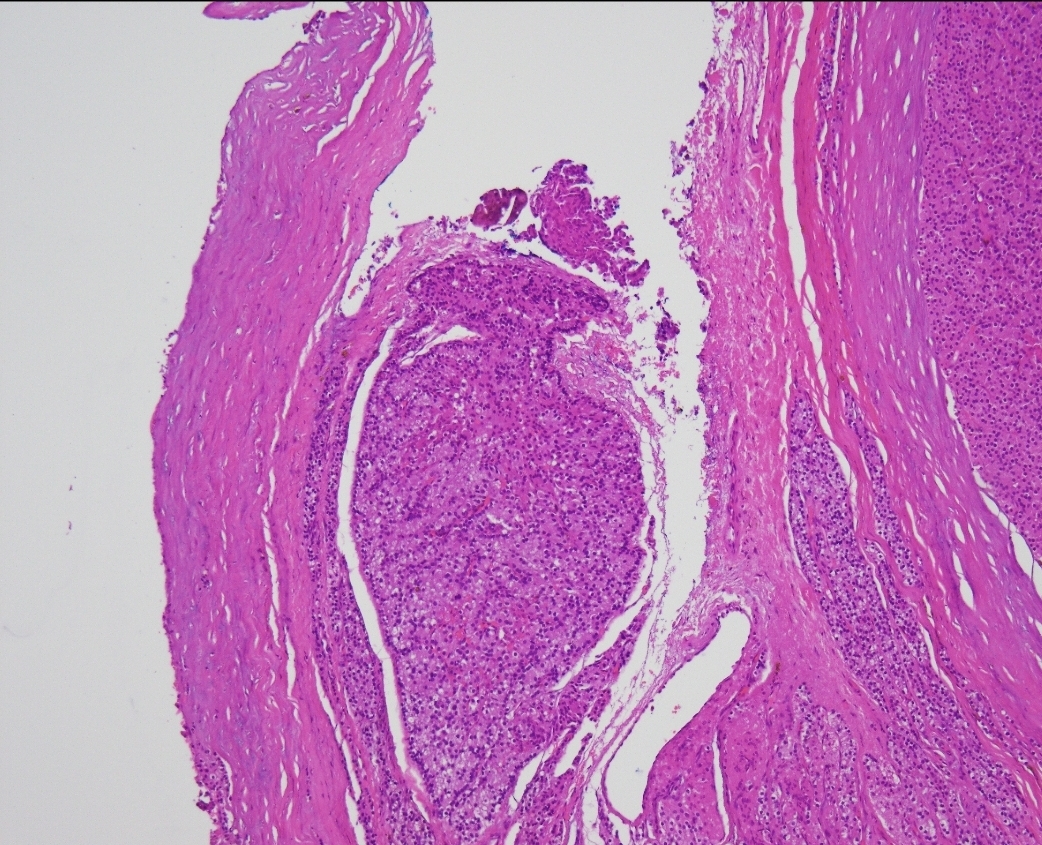

Skin lesion 40 year old male.

Who else always undertakes fumarate hydratase IHC and 2SC IHC in cutaneous leiomyomas. We always do.

Practice hint, immunohistochemistry for FH can be difficult to interpret in cutaneous leiomyomas. This is because they are always associated with small non-neoplastic nerve fibres which show positive staining even in FH deficient leiomoyomas.

In contrast 2SC is always diffusely strongly positive in FH deficient leiomyomas and 2SC is easy to interpret.

The pics below show FH (negative) and 2SC (positive).